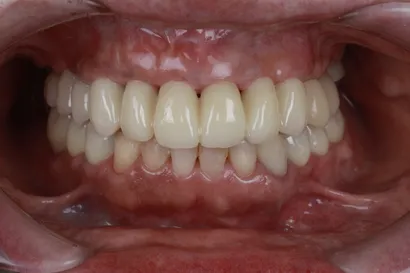

重度虫歯からの全顎インプラント治療

40代 男性

執刀医 Dr.大杉 治療内容 1回の手術でインプラントを埋め込み、即時の仮歯を装着して早期の機能回復を図りました。その後、噛み合わせを調整し、セラミックの製作を行いました。

上顎:ピンクポーセレンを用いたフルジルコニアインプラントブリッジ(All-on-4)

下顎:ピンクポーセレンを用いたフルジルコニアインプラントブリッジ(All-on-4)治療期間 1年 費用 上顎:330万 税抜

下顎:330万 税抜リスク 術後、硬い物を食べないでください。インプラントが骨に結合するまで2ヶ月かかります。この期間中に強い負荷をかけると、結合しないことがあります。 -